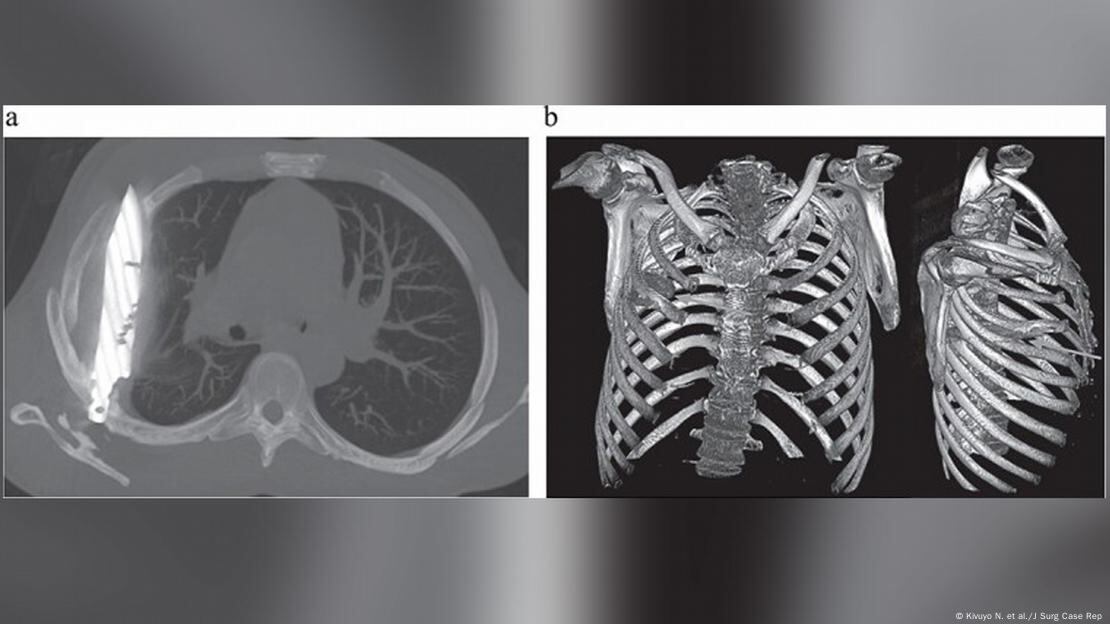

La radiografía realizada actualmente reveló un “objeto metálico retenido” dentro del tórax, pues una tomografía confirmó que se trataba de una hoja de cuchillo completa, incrustada desde la espalda hasta la parte frontal del pecho, rodeada de pus y tejido dañado.

Científicos informaron de un episodio único: un paciente pasó ocho años con un cuchillo oculto en su cuerpo. Foto: Kivuyo N. et al./J Surg Case Rep